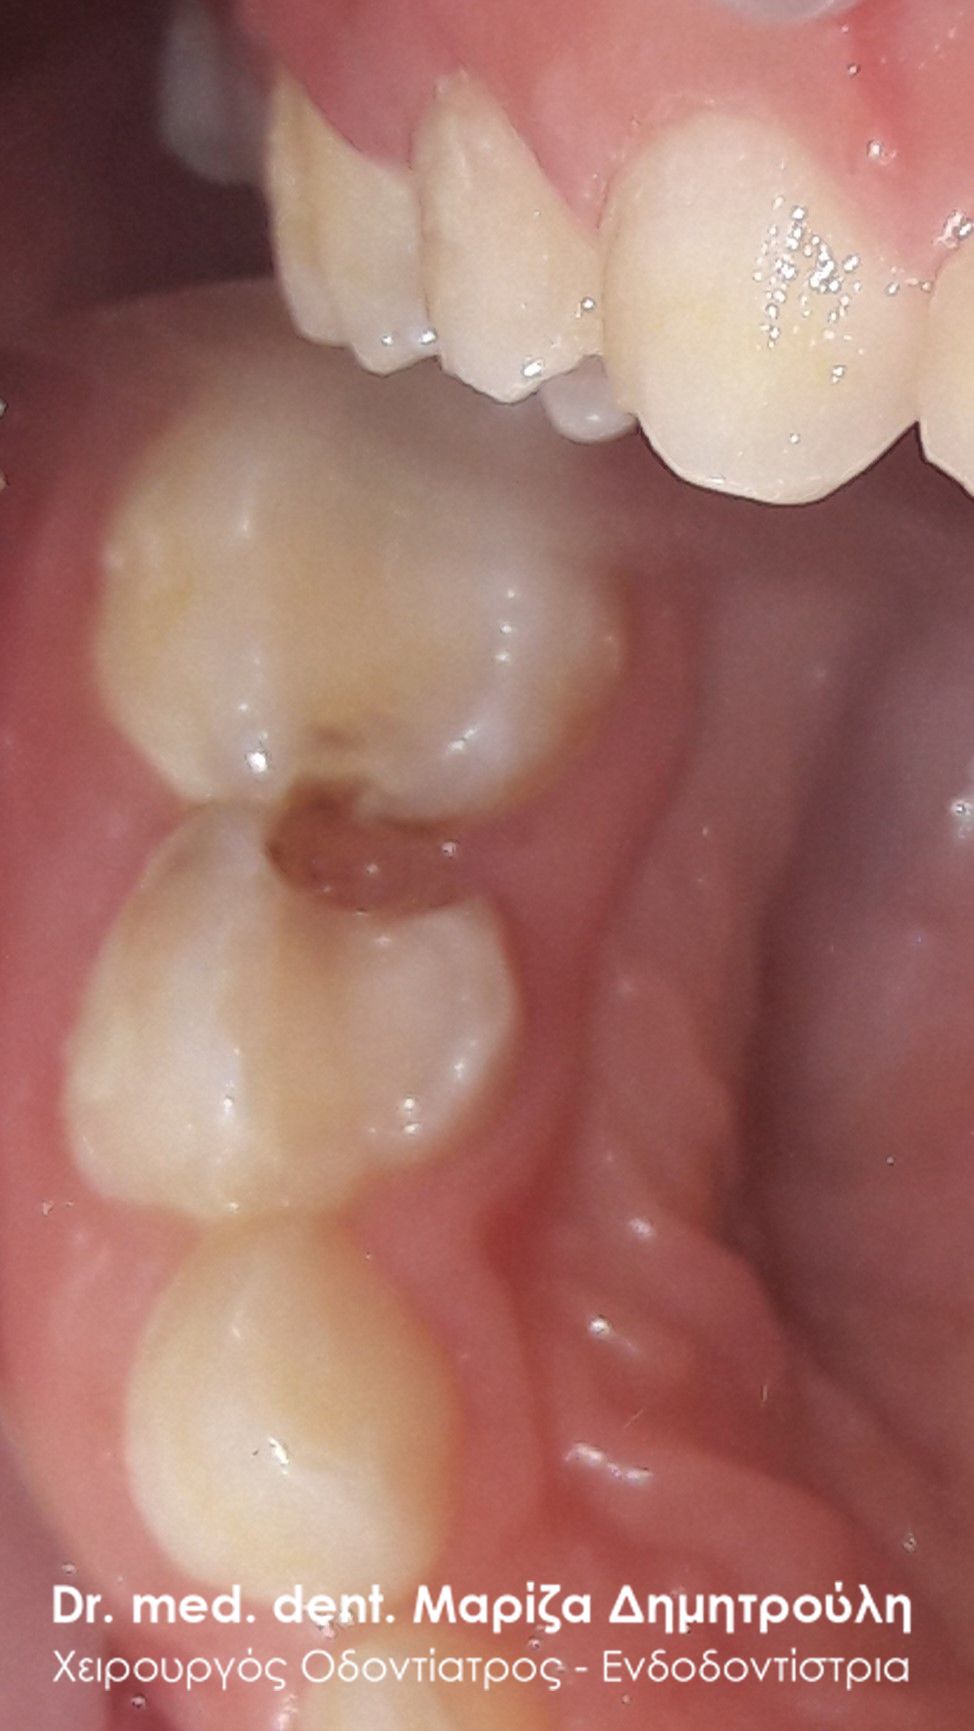

Αρχική κλινική εικόνα της δεξιάς πλευράς της άνω γνάθου

Εικόνα μετά το τρόχισμα των δοντιών

Εικόνα των δοντιών αμέσως μετά το καθάρισμα της τερηδόνας

Λευκά σφραγίσματα στη δεξιά πλευρά της άνω γνάθου με τη μέθοδο stamp technique

Αρχική κλινική εικόνα της αριστερής πλευράς της άνω γνάθου